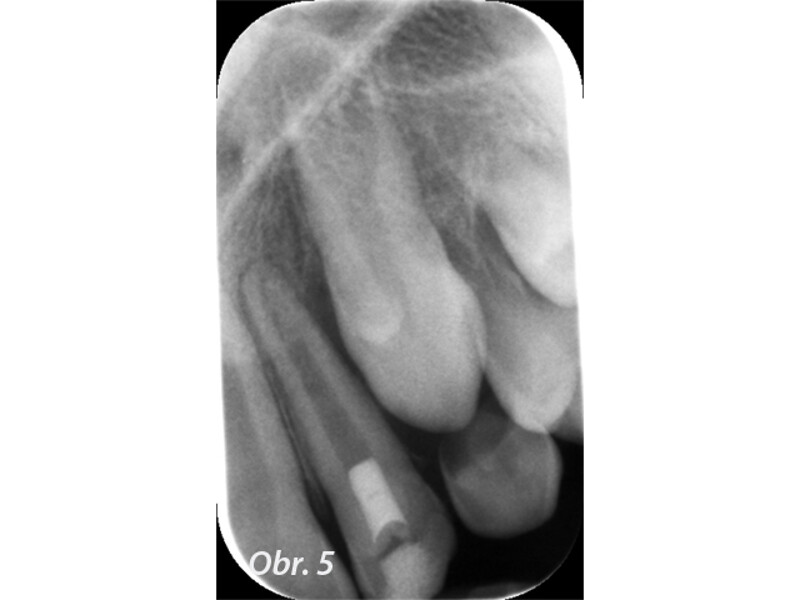

Indikační šíře MTA: Soubor kazuistik